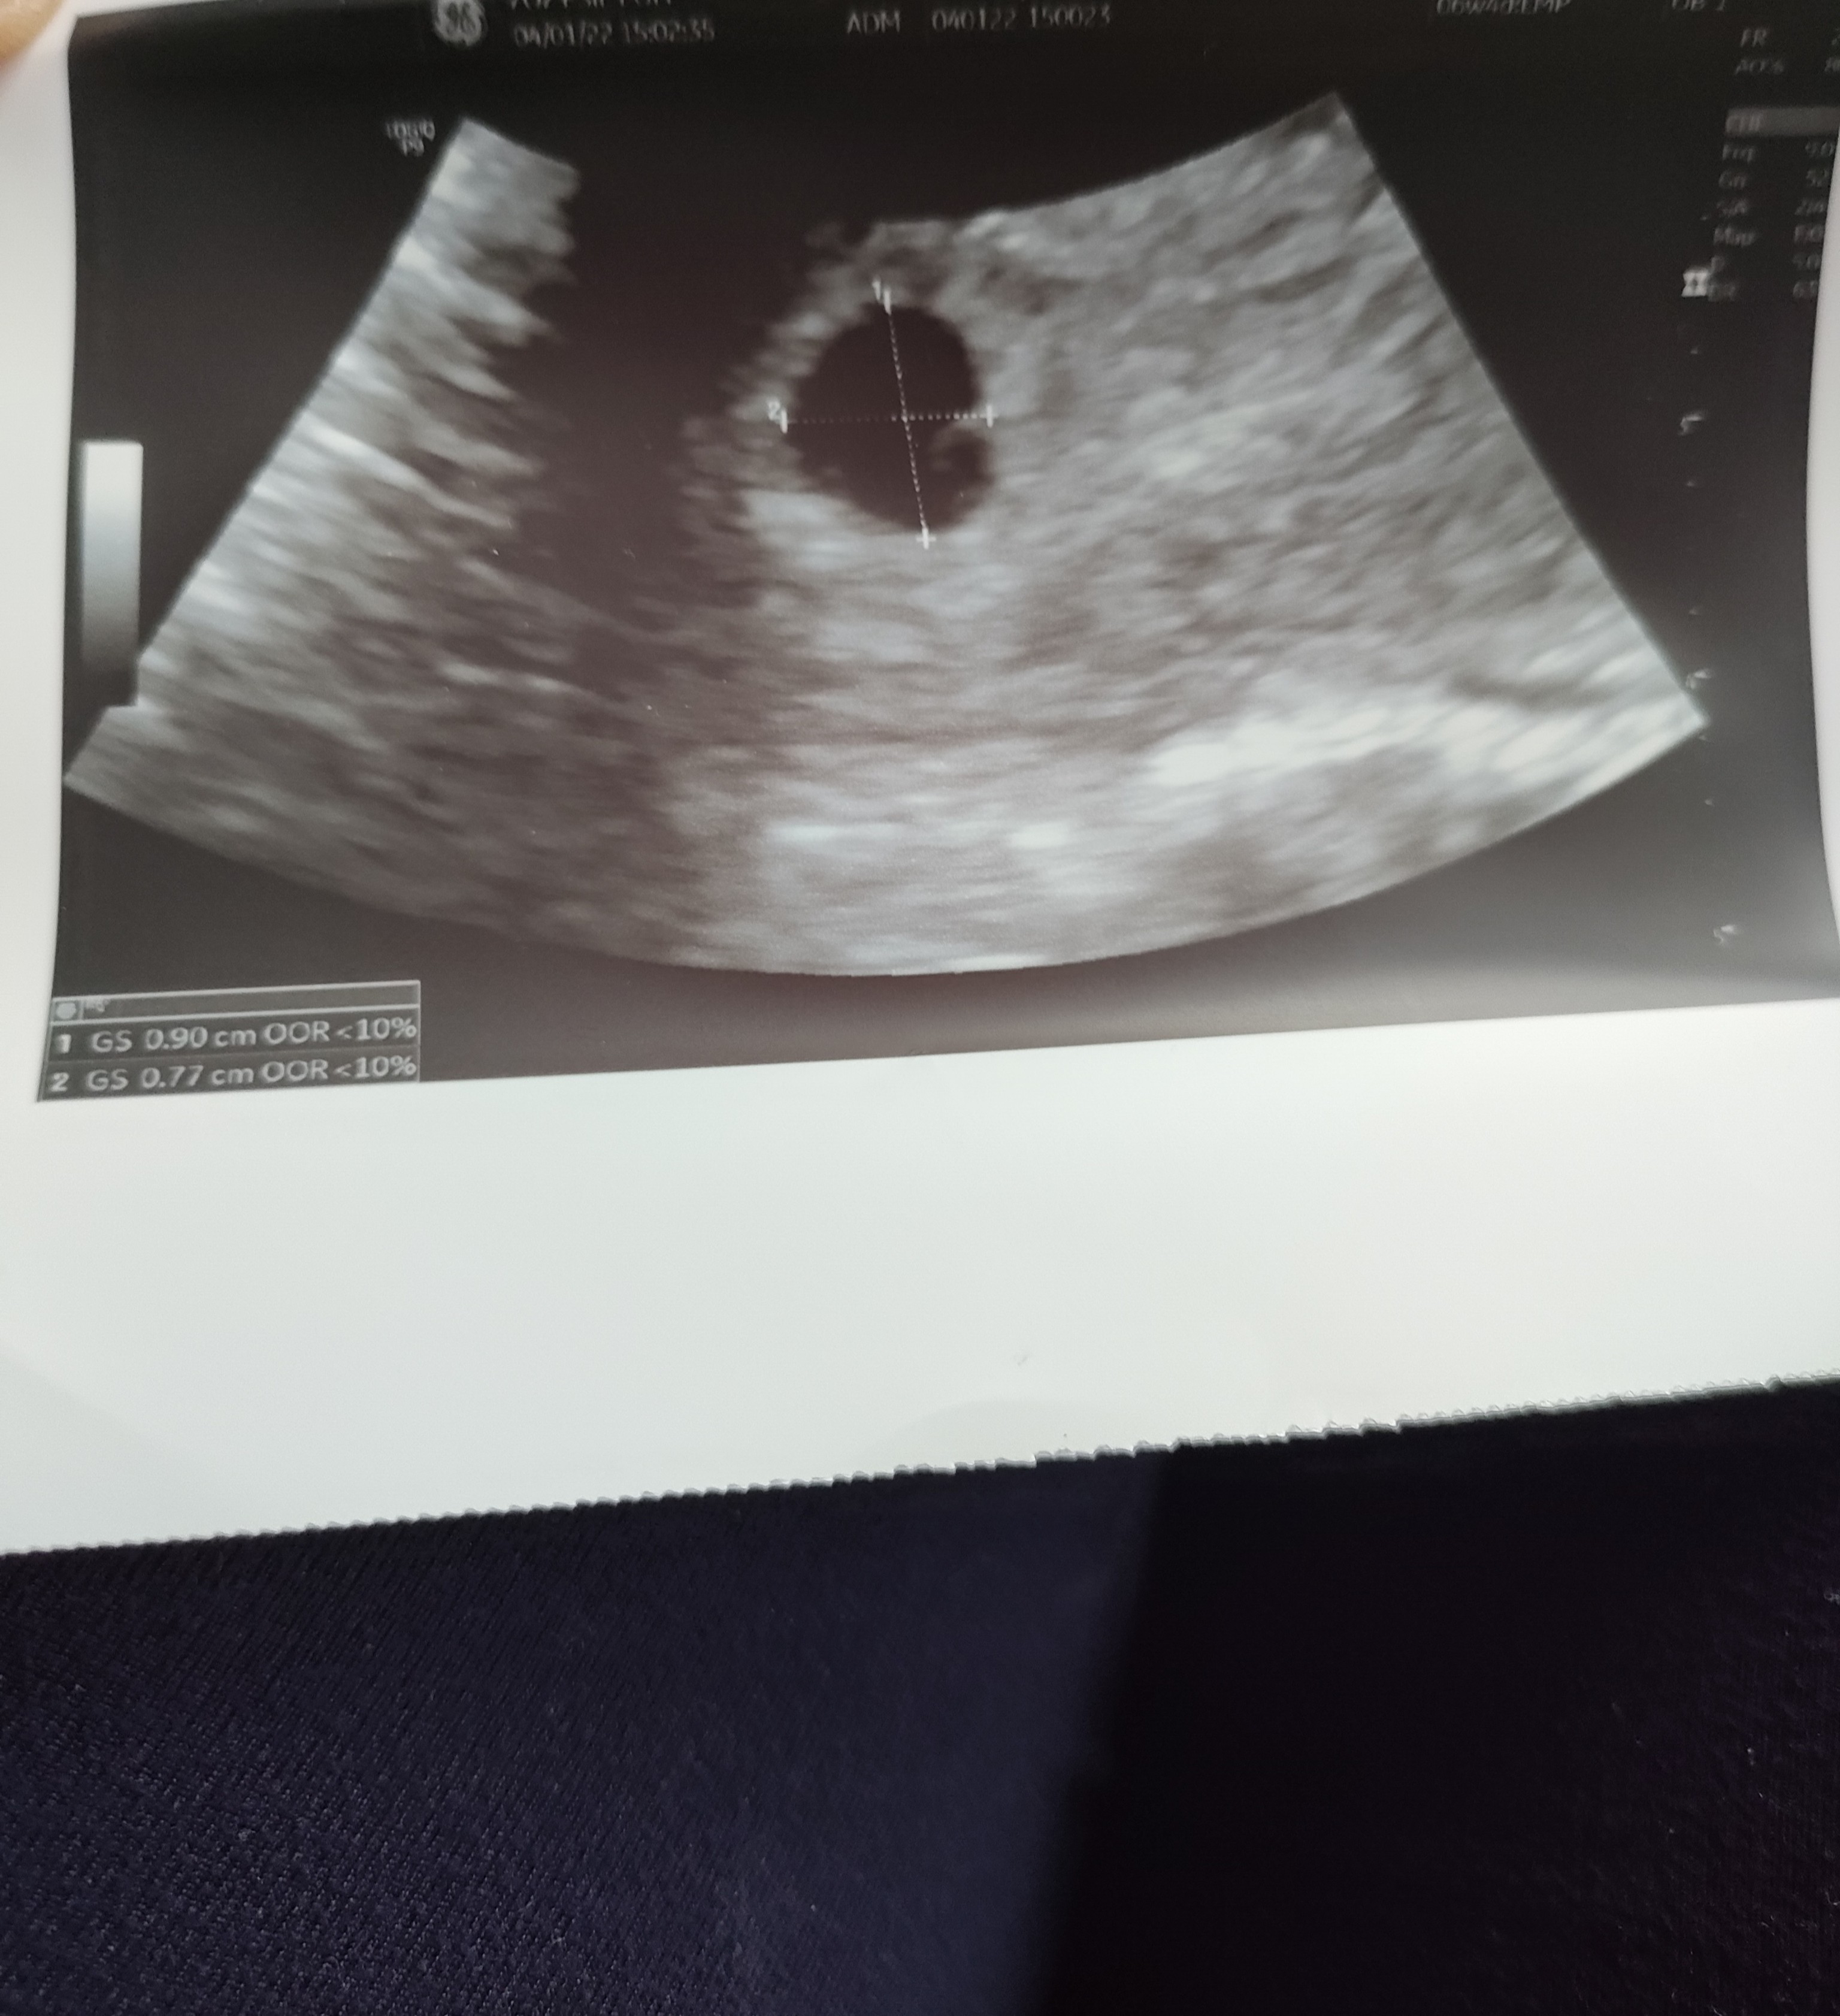

Ostatnia miesiączka 19 listopad, cykle zazwyczaj książkowe, ale od pół roku wydłużały mi się do 33 dni więc były ciut nieregularne. 22 grudnia pozytywny test, potem kolejne, beta 29.12 wynosiła 595, a w sylwestra 1219. Wizyta była 4 stycznia - ciąża młodsza o kilka dni, na USG widoczny pęcherzyk ciążowy plus żółtkowy. Następna wizyta 18 stycznia, zlecony komplet badań, plus do zrobienia ogtt przez moje poprzednie wyniki. Po pierwszym porodzie podana immunoglobulina, ja jestem rh-. Więc w tej ciąży napewno będzie kontrola przeciwciał. Pierwszy poród naturalny, bez znieczulenia, 9 dni przed terminem